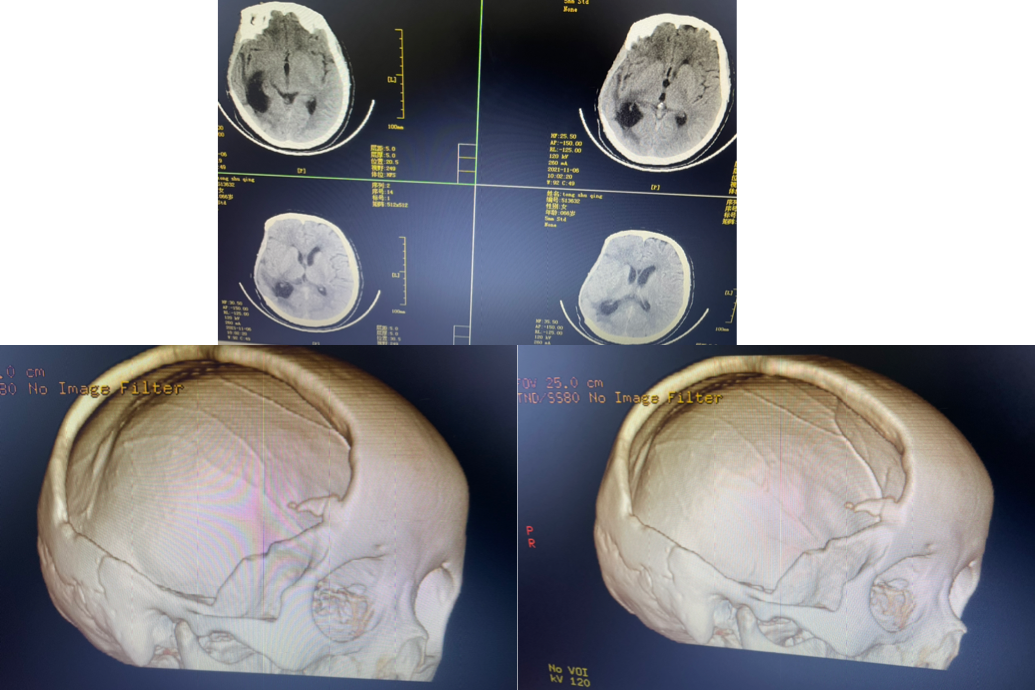

术后第一天复查

术后一月复查

术后半年来院行颅骨缺损修补

钛网颅骨修补

是目前最常用的修补材料